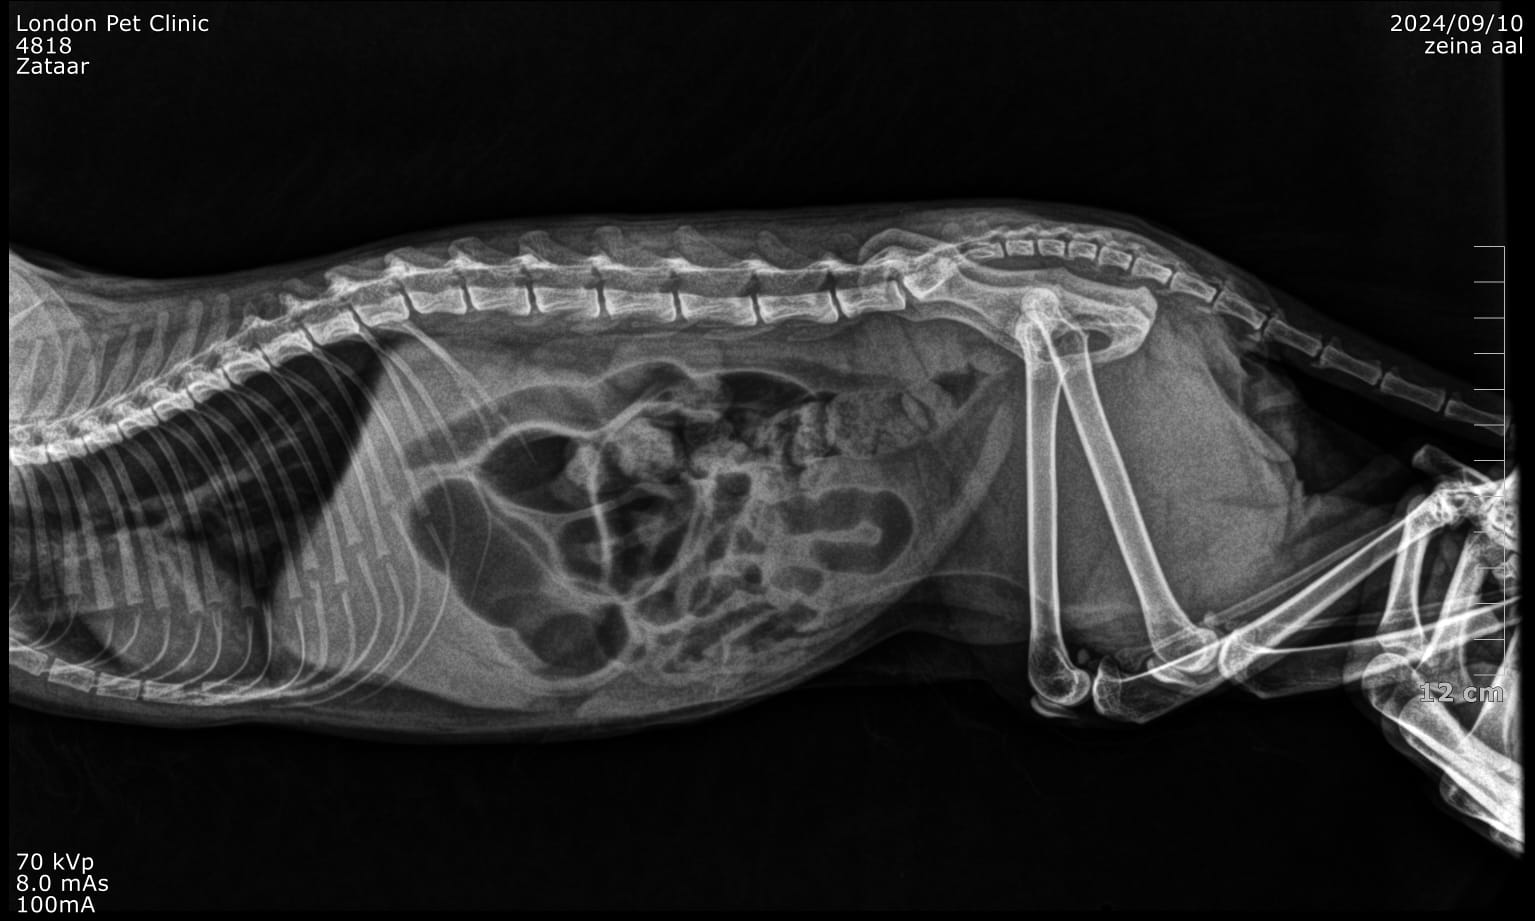

Abdominal radiographs: May show a gas--distended stomach with clogging clump

Trichobezoar causing chronic GIT signs in a 5 years old cat and lately more aggressive presentation

Large hairball lodged in the pyloric antrum